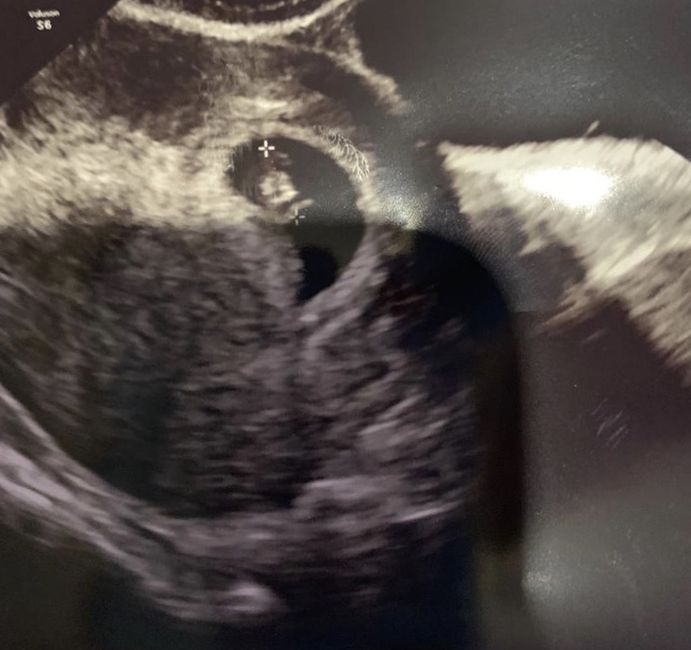

Ragazze... inizio per dirvi che non è mia L ecografia... ma ve lo chiedo per conto di terzi 😊 siamo a 6+4 prima ecografia interna.... secondo voi cosa è?! Secondo me è maschio ma chiedo a voi esperti un parere... grazie mille a chi mi aiuterà 💕♥️